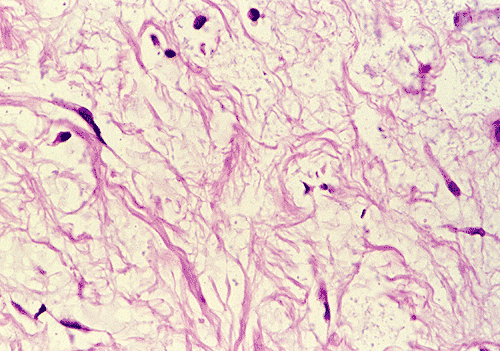

The biopsy material contained several small cores of tissue. Panel B is a low-magnification photo that showed a myxomatous lesion on one side with some linear mature bone trabeculae on the other side. This area probably represented the thinned out residual cortical bone. Panels C and D are higher magnification photos of the bone trabeculae in Panel B. No osteoclastic activity is evident. Panel E shows small, mature bone spicules that are surrounded by myxomatous tissue. The hypocellular and myxomatous nature of the lesion is well demonstrated in Panel F. Panel G and H are high magnification photos from different areas and show a modest number of collagen fibers within a myxomatous background. The bland features of the tumor cells are also well illustrated.